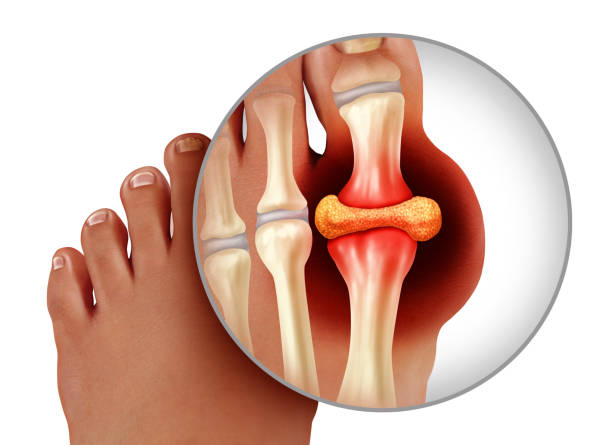

통풍이란 질병은 몸 속 요산이라는 물질이 쌓이면서 그 요산이 우리 몸에서 염증 반응을 일으켜 몸에서 관절염과 심한 통증, 또 콩팥이 망가지는 질환이자 자가 염증질환으로 알려져 있으며 주로 발가락, 발등과 같은 관절에 나타나 통풍이 생긴 경우 다리를 절단하고 싶을 정도로 아주 극심한 통증을 유발하는데 더 무서운 점은 치료시기를 놓치면 말기신부전, 뇌졸중, 심근경색 등 생명을 위협할 수 있는 합병증을 유발합니다.

통풍 증상 원인과 관련하여 가장 많이 등장하는 물질은 ‘요산’으로 이 ‘요산’이 체내에 과다하게 쌓이면 통풍이 오게되는데 이 ‘요산’은 소변으로 나오는 산성물질이라는 의미로 고기나 생선류에서 많이 들어있는 필수아미노산 중 하나인 퓨린이 에너지로 사용되고 소변을 통해 찌꺼기 형태로 나가는 형태인데 적당한 시기에 체외로 배출을 하지 못한다면 이 요산과 나트륨이 결합하여 요산염 나트륨으로 화학적 결합을 하게됩니다.

이 화학적 결합은 체내 백혈구가 세균이나 바이러스로 인식해 잡아먹는데 이 과정에서 백혈구 안에 있는 염증 반응 물질을 터트리며 백혈구 속 염증 반응 물질이 지속적으로 터져 아주 심하게 염증과 통증을 느끼게 되는 것입니다. 따라서 우리 식습관과 밀접한 연관이 있는 통풍은 주로 새우젓, 동물내장 등 퓨린이 많은 들어간 음식을 즐긴다거나 맥주 등을 즐겨 요산 배출 장애가 발생하면 통풍에 걸리게 됩니다.

통풍 증상은 그 시기에 따라 고요산혈증, 급성 통풍성 관절염, 간헐기 통풍 등 3가지 단계로 나눌 수 있으며 전형적 증상은 갑자기 엄지발가락 부위가 조금 뻐끈하다는 느낌으로 시작하며 이 부위가 급격히 붓고 통증이 심해지면 관절 주변 피부가 일어나면 열감이 느껴지고 종국에는 신발을 신을 수 없을 정도로 극심한 통증을 겪게 됩니다.